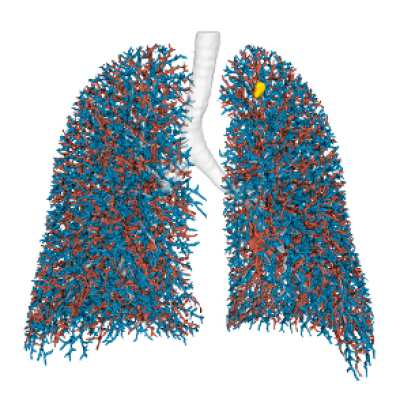

Built on advanced capabilities in lung segmentation and quantification, our AI technology interprets thoracic CT data with anatomical precision - capturing airway trees, parenchymal patterns, and vascular structures, even in severely diseased lungs.

- Segmentation of anatomical structures up to sub-segmental level

- Anatomical mapping to support navigation planning and guidance